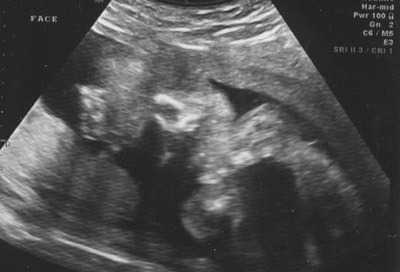

They started with the general level II ultrasound showing different body parts and organs of the baby. Time was taken to measure things like the amount of amniotic fluid, the size of the head and stomach, and the general size of the baby. Everything looked as it should even down to measuring within one day of my due date. The baby appears to weigh about 1 lb. 3 oz. by their measurements. The only thing that was remotely odd was the position the baby was in, though that won't present a problem unless the baby decides to try to be born this way. Basically he/she was breech with one leg held all the way up to the head. Here are some pictures:

Face looking straight at it, with the foot directly below the chin: